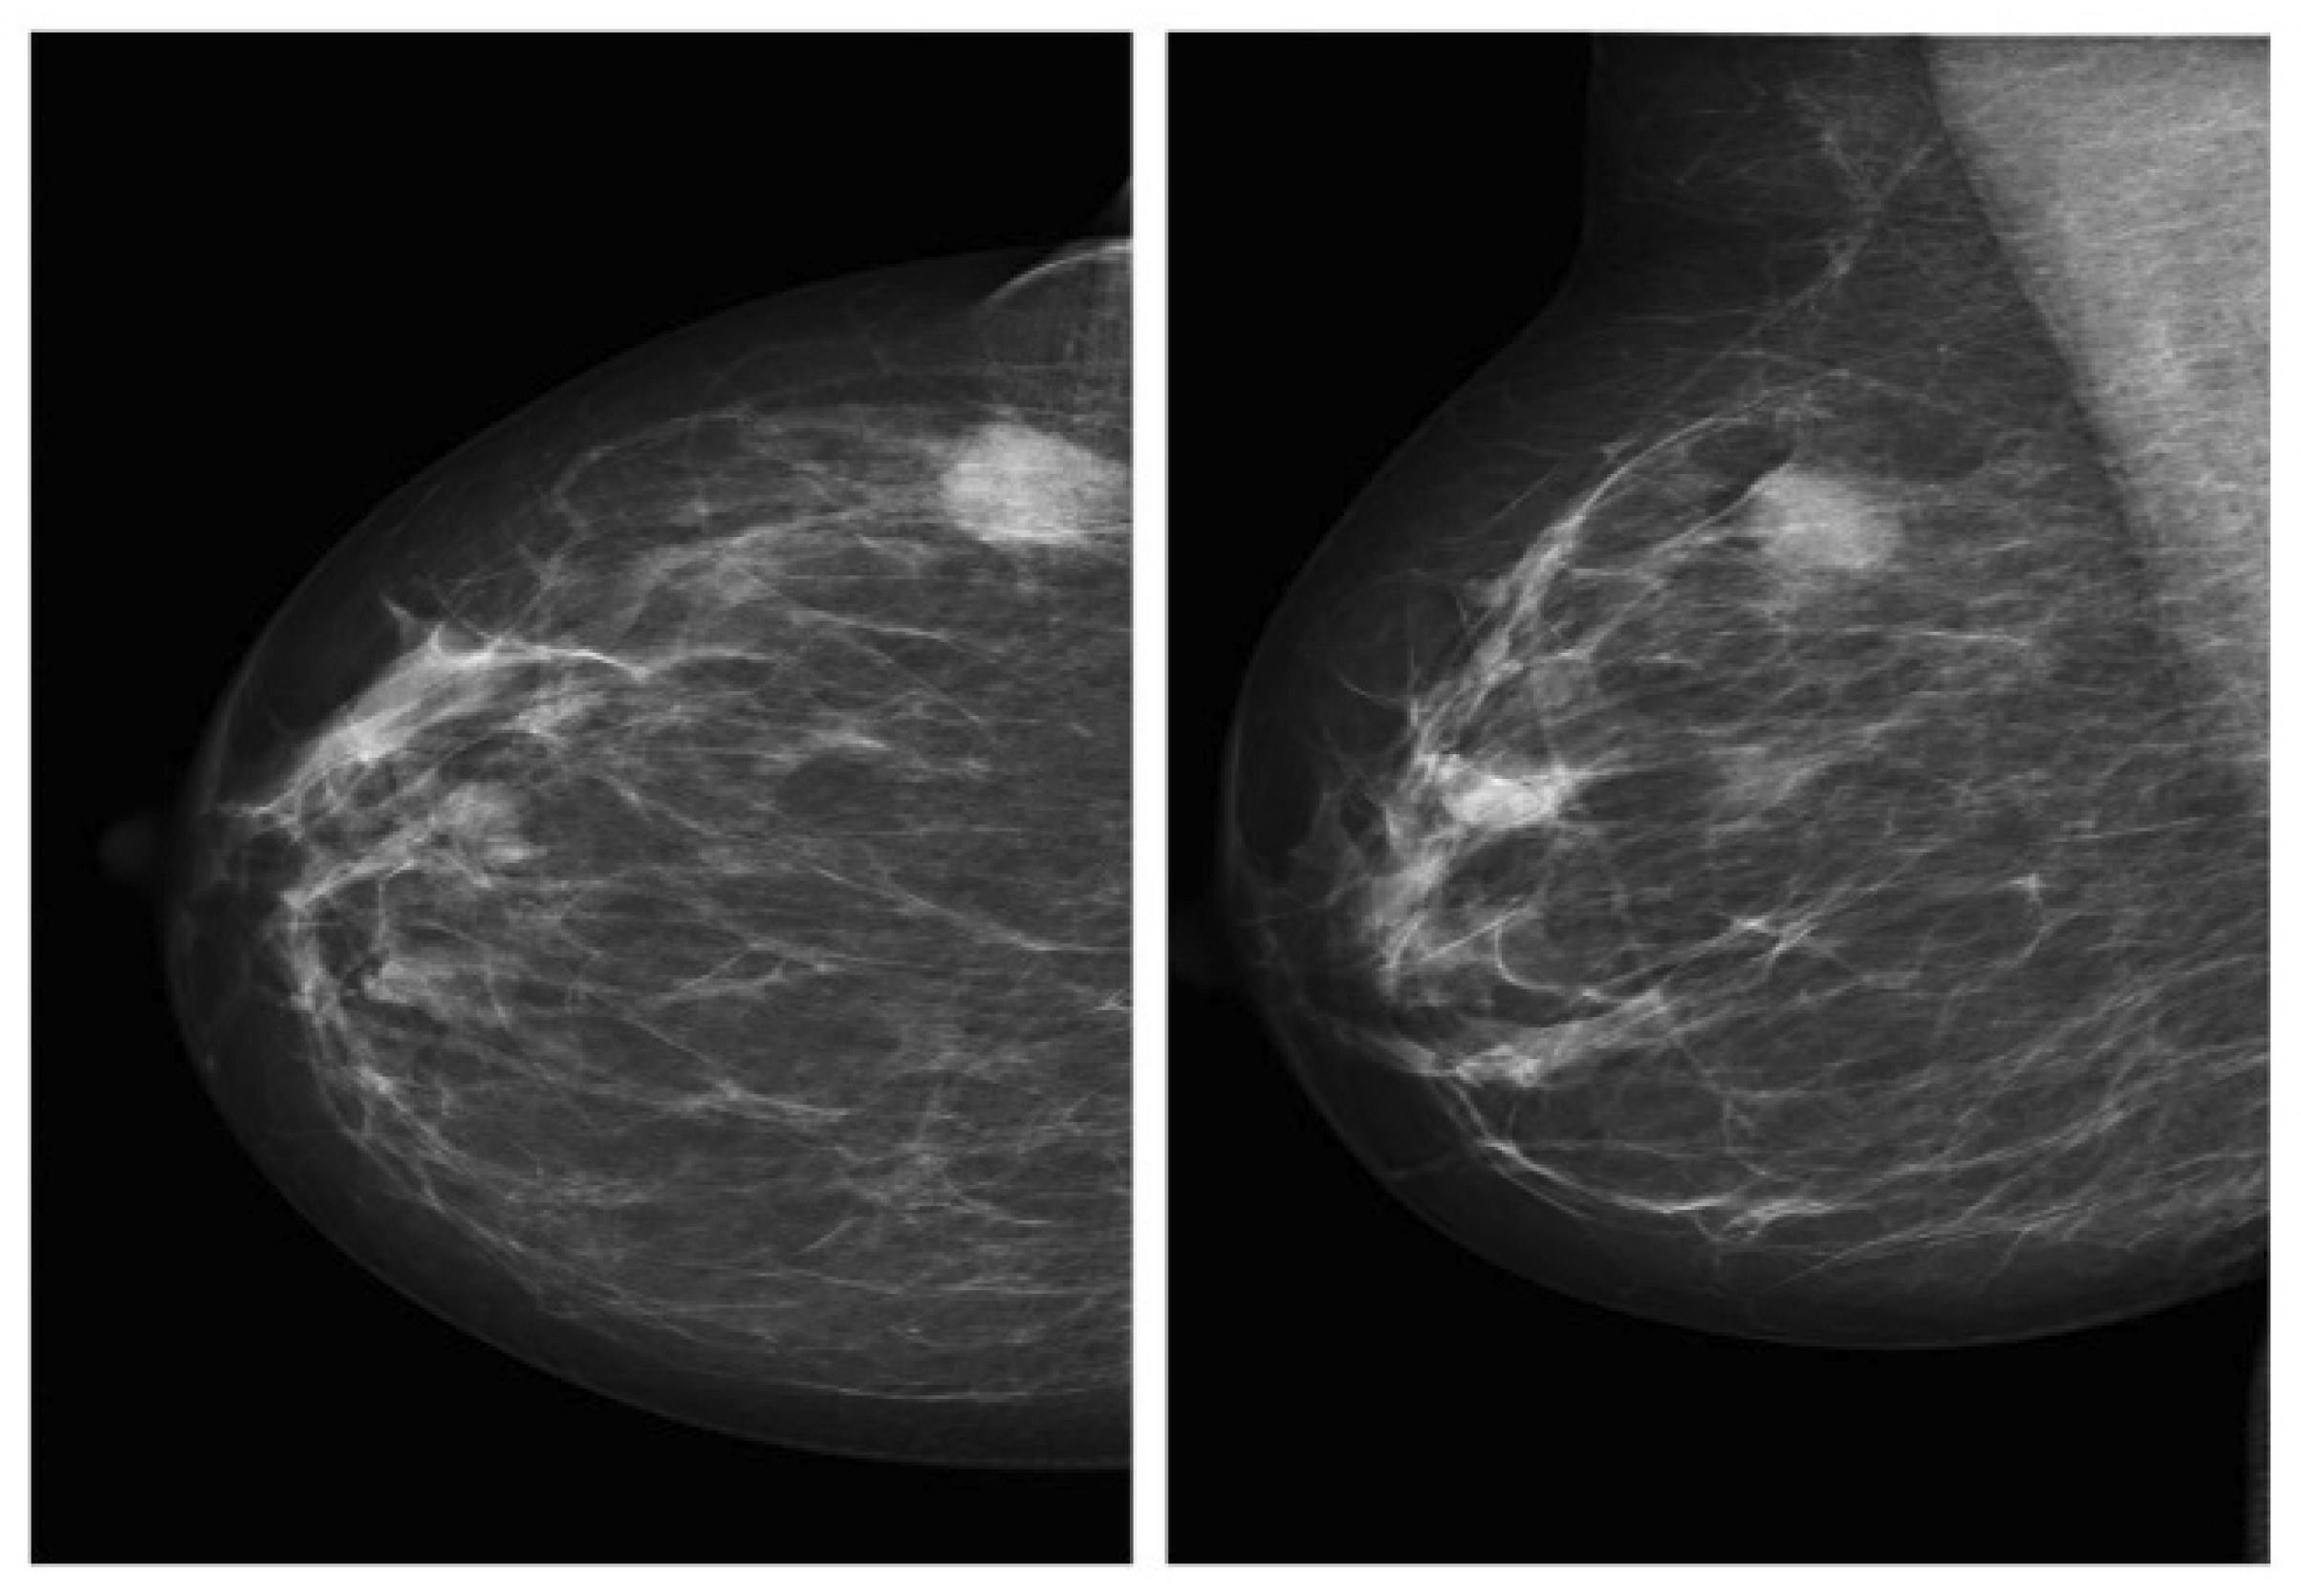

One of the most significant characteristics of a mammogram is the utilization of low-energy X-rays, to screen and diagnose the human breast. Two master views are introduced for acquiring the X-ray images: CC and MLO (Figure 2). Mammography mainly aims to detect BC early [35,36], ordinarily by detecting abnormal regions or masses in the images of the X-ray. These masses are often highlighted by a physician or an expert radiologist.

DDSM is employed to conduct research in the systems of detecting and classifying BC. It shows real breast data with a resolution of 42 microns, 16 bits, and an average size of 3000 × 4800 pixels. It [15,36,39] holds 2620 scanned film mammography studies distributed in 43 volumes. DDSM database holds 695 normal cases and 1925 abnormal cases (914 malignant/cancer cases and 870 benign cases, as well as 141 benign without callback), specifying the boundaries and locations of the abnormal cases. For every case, four images can be found to represent the left and right breasts in the MLO and CC views (Figure 2) [34]. An experienced radiologist can recognize malignant and benign masses in all mammograms. CBIS-DDSM Dataset: CBIS-DDSM is a developed and united edition of DDSM. Table 3 displays the distribution of data.

Figure 2. Mammography in CC and MLO views, respectively.